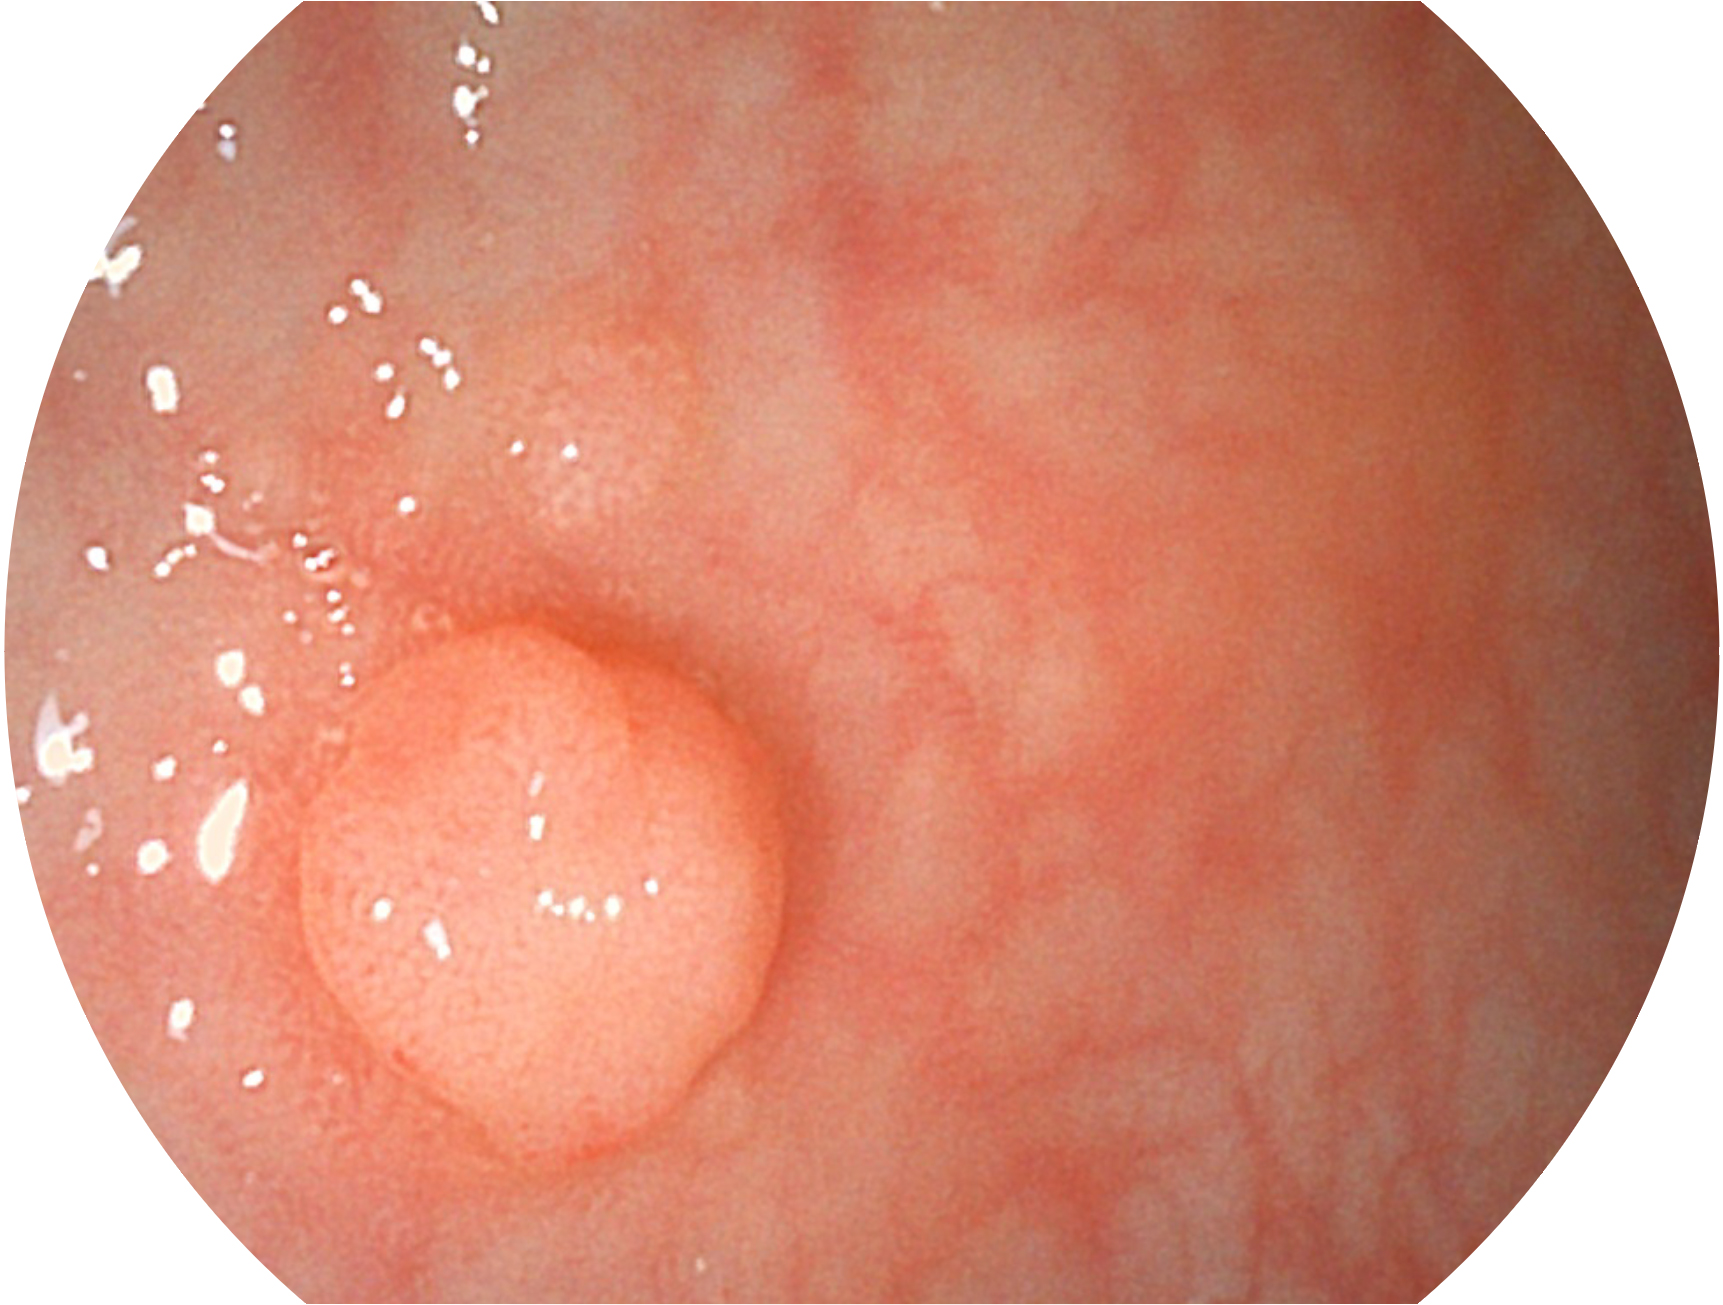

哈哈体育官网新开发的内镜染色技术,主要是基于多波长LED 光源的开发,VLS-55Q 四波长LED 光源是由四个不同颜色的LED光按照相应照明模式所规定的特定发光比例进行合束后形成,合束后形成的照明光的光谱由红光、绿光、蓝光及蓝紫光这四个不同的波段范围构成。具有更高光谱自由度,通过光谱比例的控制,实现了聚谱成像技术,英文全称为“Spectral Focused Imaging, SFI”,缩写为“SFI”和光电复合染色成像技术,英文全称为“Versatile Intelligent Staining Technology, VIST”,缩写为“VIST”。